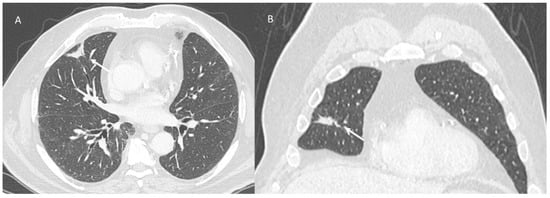

2.2. Pneumonitis COVID-19

| Type of Pneumonia | Lung Involvement | CT-Patter |

|---|---|---|

| COVID-19 Pneumonia | Diffuse (related to the phase of disease) | ground-glass opacity, crazy-paving pattern, consolidative opacities, interlobular septal thickening (according to the phase of disease) |

| RRR-Related Vaccine | Target Area | Consolidative opacities |

| Pulmonary lymphangitis carcinomatosa | Diffuse (related to the phase of disease) | Irregularly interlobular septal thickening, smooth (early stage), or nodular thickening (late development), ground-glass opacity, pleural effusions. |

| ICI-Related Pneumonitis | Diffuse (related to the phase of disease) | ground-glass and reticular opacities, consolidative opacities, interlobular septal thickening, “crazy-paving” pattern |